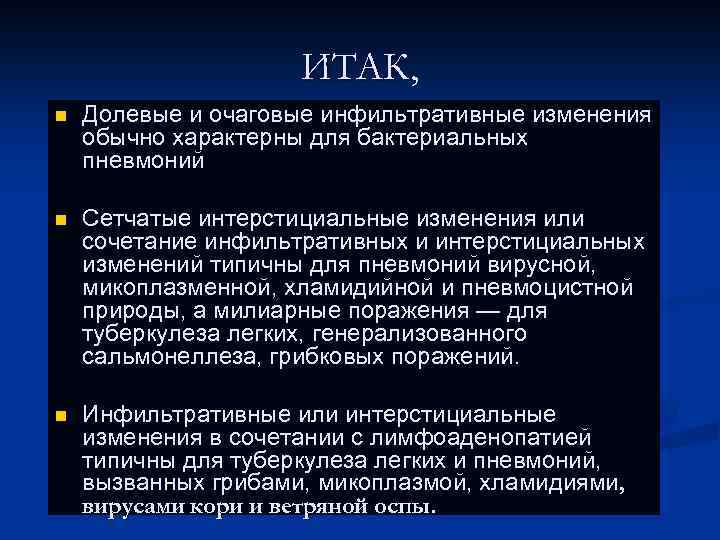

ИТАК, n Долевые и очаговые инфильтративные изменения обычно характерны для бактериальных пневмоний n Сетчатые интерстициальные изменения или сочетание инфильтративных и интерстициальных изменений типичны для пневмоний вирусной, микоплазменной, хламидийной и пневмоцистной природы, а милиарные поражения — для туберкулеза легких, генерализованного сальмонеллеза, грибковых поражений. n Инфильтративные или интерстициальные изменения в сочетании с лимфоаденопатией типичны для туберкулеза легких и пневмоний, вызванных грибами, микоплазмой, хламидиями, вирусами кори и ветряной оспы.